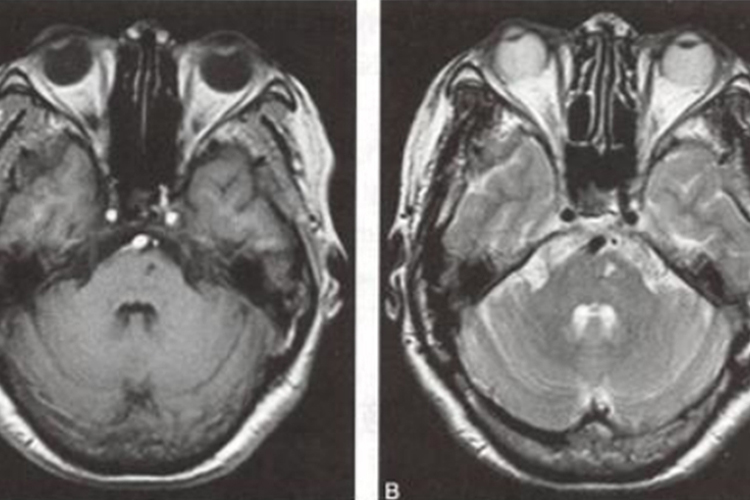

多数患者发病24小时后脑CT逐渐显示低密度梗死灶,发病后2-15日可见均匀片状或楔形的明显低密度灶。MRI可清晰显示早期缺血性梗死,梗死灶T1呈低信号、T2呈高信号。

小动脉闭塞型脑梗:又称腔隙性缺血性脑卒中,患者多有高血压病史,突然或逐渐起病,出现偏瘫或偏身感觉障碍等局灶症状,表现为麻木、烧灼、刺痛,以及吞咽障碍、构音障碍等,无头痛、颅内压增高和意识障碍等表现。通常为在进行MRI检查后,明确脑梗灶。